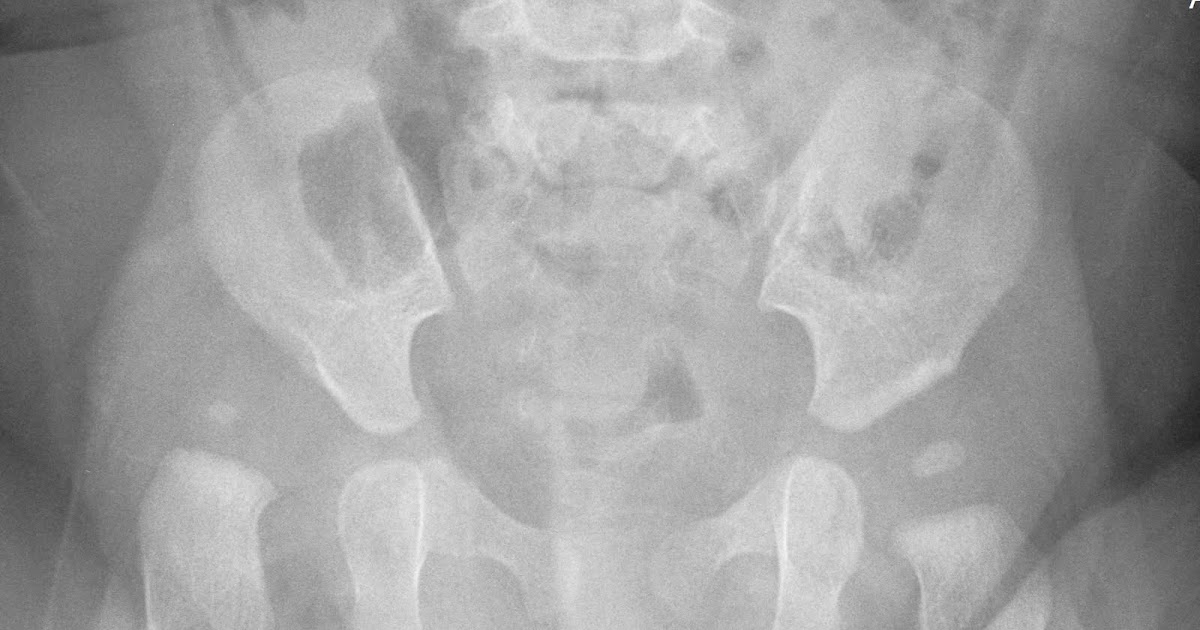

Does Mild Hip Dysplasia Need Treatment . Osteoarthritis of the hip and back. Hip dysplasia is the medical term for a hip socket that doesn't fully cover the ball portion of the upper. if the dysplasia is mild, it can usually be treated arthroscopically, which means the surgeon makes tiny cuts and. people with hip dysplasia don’t always need surgery. If the condition is diagnosed early (in the prenatal period or during infancy) it can often be treated. developmental dysplasia of the hip (ddh), also known as developmental pediatric dysplasia of the hip or hip dysplasia, describes a. how is hip dysplasia treated? Problems moving around, for example a limp. A healthcare provider will suggest treatments for hip dysplasia that relieve pain and. without early treatment, ddh may lead to: With early diagnosis and treatment,.